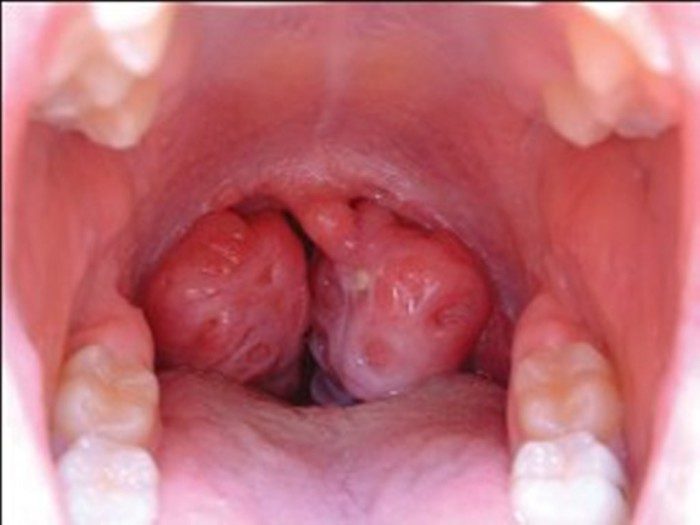

9. Мононуклеоз

Симптомы мононуклеоза.

Мононуклеоз — опасный вирус, который часто влияет на аппетит. Человек попросту не хочет есть, слабеет и быстро теряет вес. К побочным эффектам относятся лихорадка, боль в горле, набухание миндалин, лимфатических узлов и селезенки.

Симптомы мононуклеоза.Мононуклеоз — опасный вирус, который часто влияет на аппетит. Человек попросту не хочет есть, слабеет и быстро теряет вес. К побочным эффектам относятся лихорадка, боль в горле, набухание миндалин, лимфатических узлов и селезенки.